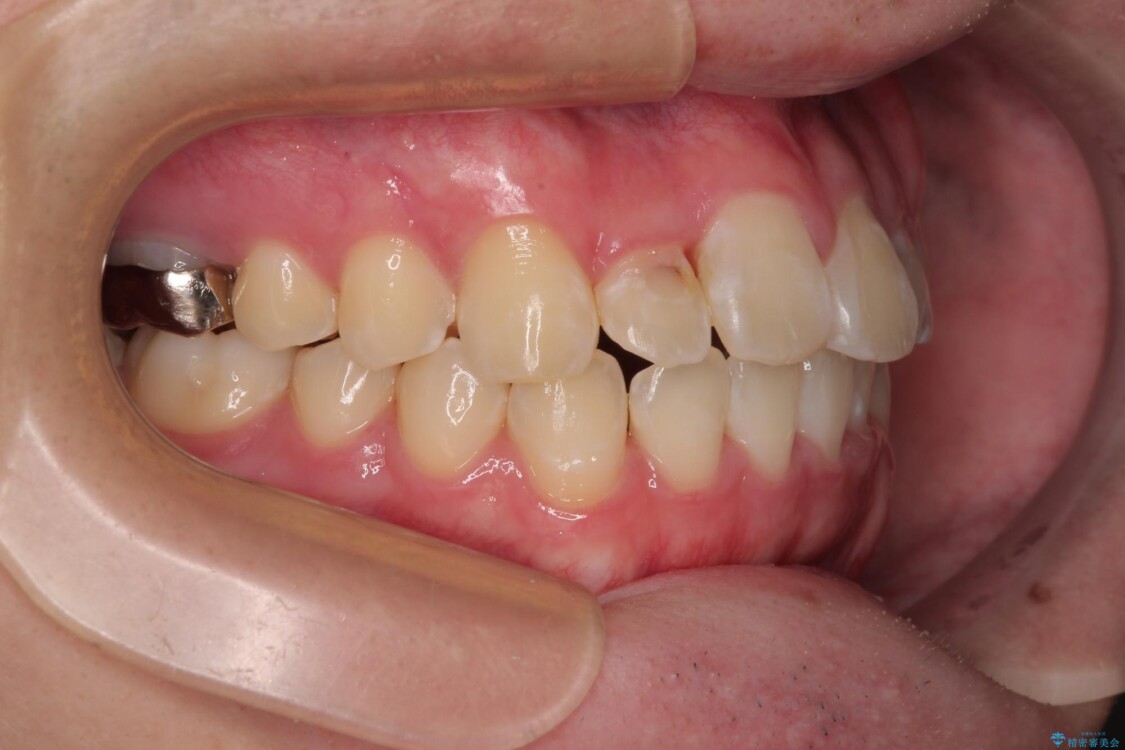

「歯並びがデコボコしていて、上下の中心がズレているのが気になる…」という悩みで来院された患者さまの症例をご紹介します。

初診時の状態

・上下ともに歯がきれいに並びきらず、がたつきが見られました。

・上下の前歯の中心(正中)がずれています。

・特に上顎の幅が狭いため、下顎の歯列も内側に入り込み、歯が並ぶスペースが不足していました。

治療前

• 1年でここまで変わる!歯列のがたつきと正中のズレを改善した矯正治療(メタルブラケット×MARPE) 治療前画像